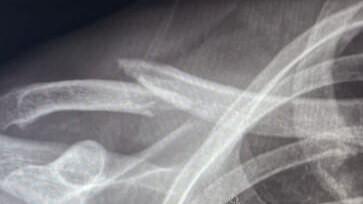

Een goed resultaat Sleutelbeen fractuur Lees meer

Sleutelbeen fractuur Sleutelbeen fractuur